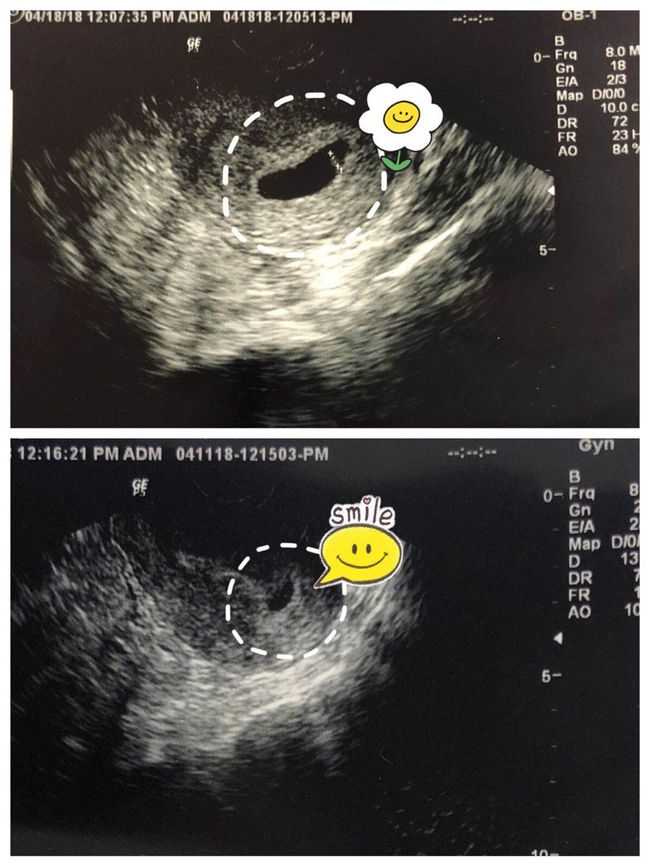

孕妇应定期进行产前检查,以便及时发现并处理孕期用药问题。